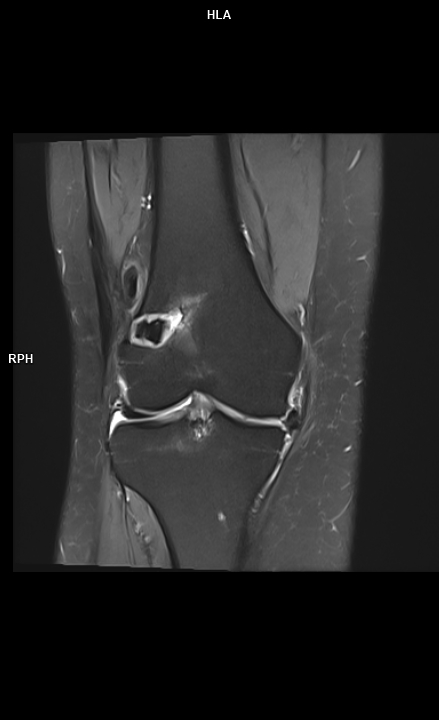

Figura 4:  coronal PD cu cu saturaţia grăsimii

Discuţie caz nr 107: la nivelul platoului tibial și posterior la nivelul condilului femural extern se evidențiază modificări de tip chistic în osul subcondral. În plus, a nivelul ligamentului colateral lateral se evidențiază o plajă limitată de lipsă de substanță în dreptul unei plaje de lipsă de substanță osoasă din condilul femural extern care este plombată postoperator.